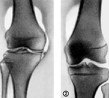

Пневматическая артрография. Диагностический метод, заключающийся во введении углекислого газа или кислорода в сустав атмосферного воздуха с последующей серией рентгеновских лучей. Газ вводится в суставную полость в чистой гардеробной, наблюдая за правила асептики и антисептики. Исследование может обнаружить даже незначительные патологические изменения, которые не появляются на обычных рентгеновских лучах. Противопоказаниями к пневмоартрографии являются неудовлетворительное состояние больного, раны и ссадины в области исследуемого сустава.